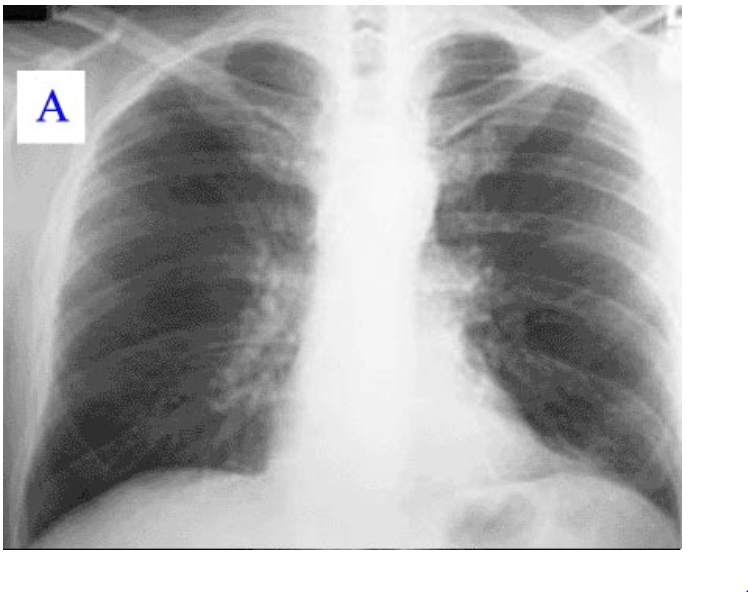

Radiographic and CT Features of Viral Pneumonia RadioGraphics